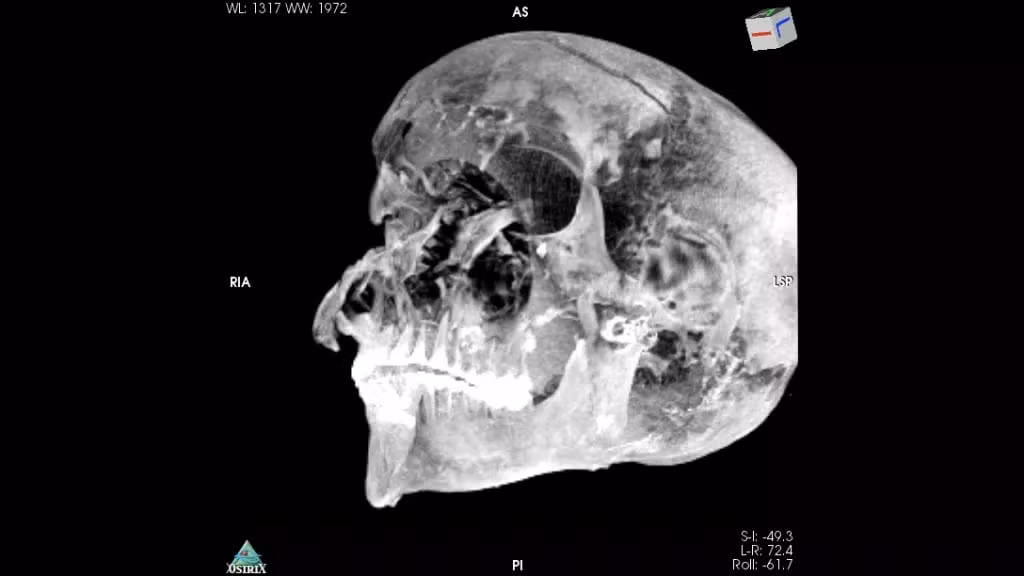

Sau khi tìm thấy xác ướp, các chuyên gia có những phát hiện bất ngờ về thi hài của ông. Trong số này, hộp sọ của pharaoh Seqenenre Taa II có một vết thương lớn dài 7 cm ở vùng trán.

Ông hoàng nổi tiếng Ai Cập này còn có một số vết thương ở mũi, má và mắt phải.

Kết quả kiểm tra xác ướp của các chuyên gia hé lộ Seqenenre Taa II có đôi tay biến dạng. Đây được cho là bằng chứng về việc ông bị trói 2 tay sau lưng.

Vì ở trong tư thế này nên ông hoàng Seqenenre Taa II không thể tránh được cú tấn công chí mạng vào đầu.

Căn cứ vào tình trạng vết thương, Seqenenre Taa II quỳ gối khi bị hành quyết bằng vũ khí như rìu, kiếm...